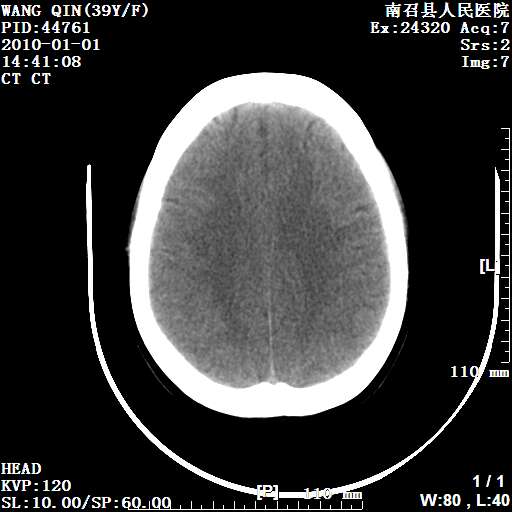

以下是引用随光逐影在2010-1-22 9:03:00的发言:[br]考虑左侧中颅窝(蝶骨翼区)脑膜瘤侵犯蝶骨翼并突入左侧眼眶。

以下是引用水过无痕在2010-1-22 14:55:00的发言:[br]一、定位:颅外占位;二、定性:恶性可能性大;三、组织来源:来源于左侧眼外直肌或其他部位;考虑为:横纹肌肉瘤>转移瘤>脑膜瘤.